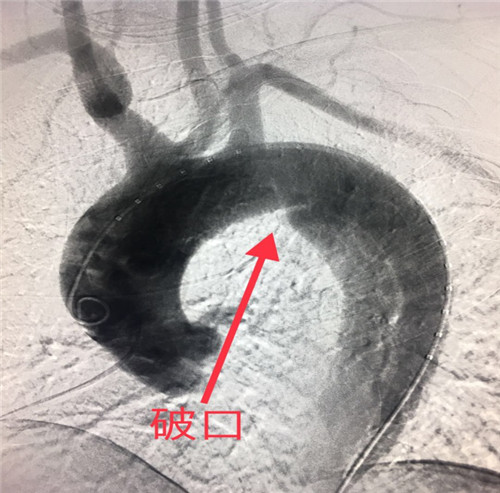

患者,男性42岁,患高血压数年,常年在外务工,以“突发剧烈背痛”在当地医院就诊并行胸部CT平扫及胸主动脉血管成像检查,CTA提示主动脉夹层、破口位于左锁骨下动脉远端,诊断为主动脉夹层,患者家属电话与MILAN.COM介入科李建国主任联系,由当地120转入我院,患者胸背部剧烈疼痛、情绪血压极不稳定,随时有破裂死亡风险,命悬一线。李建国主任反复叮嘱,在转院途中务必控制好心率、血压。

胸主动脉夹层起病急、发展快、死亡率极高,若不及时有效治疗,48小时内死亡率70%左右,一周内的死亡率高达90%左右。该患者胸主动脉夹层破口距离左锁骨下动脉开口不足1厘米,为患者实施覆膜支架成功修复腔内破口、部分保留左锁骨下动脉避免了术后出现左上肢无脉症、脑缺血等严重并发症,该术式是目前主动脉夹层介入治疗的首选,较传统外科开胸手术创伤大、高风险、术后恢复慢,介入覆膜支架植入术具有微创、高效、安全等优势。